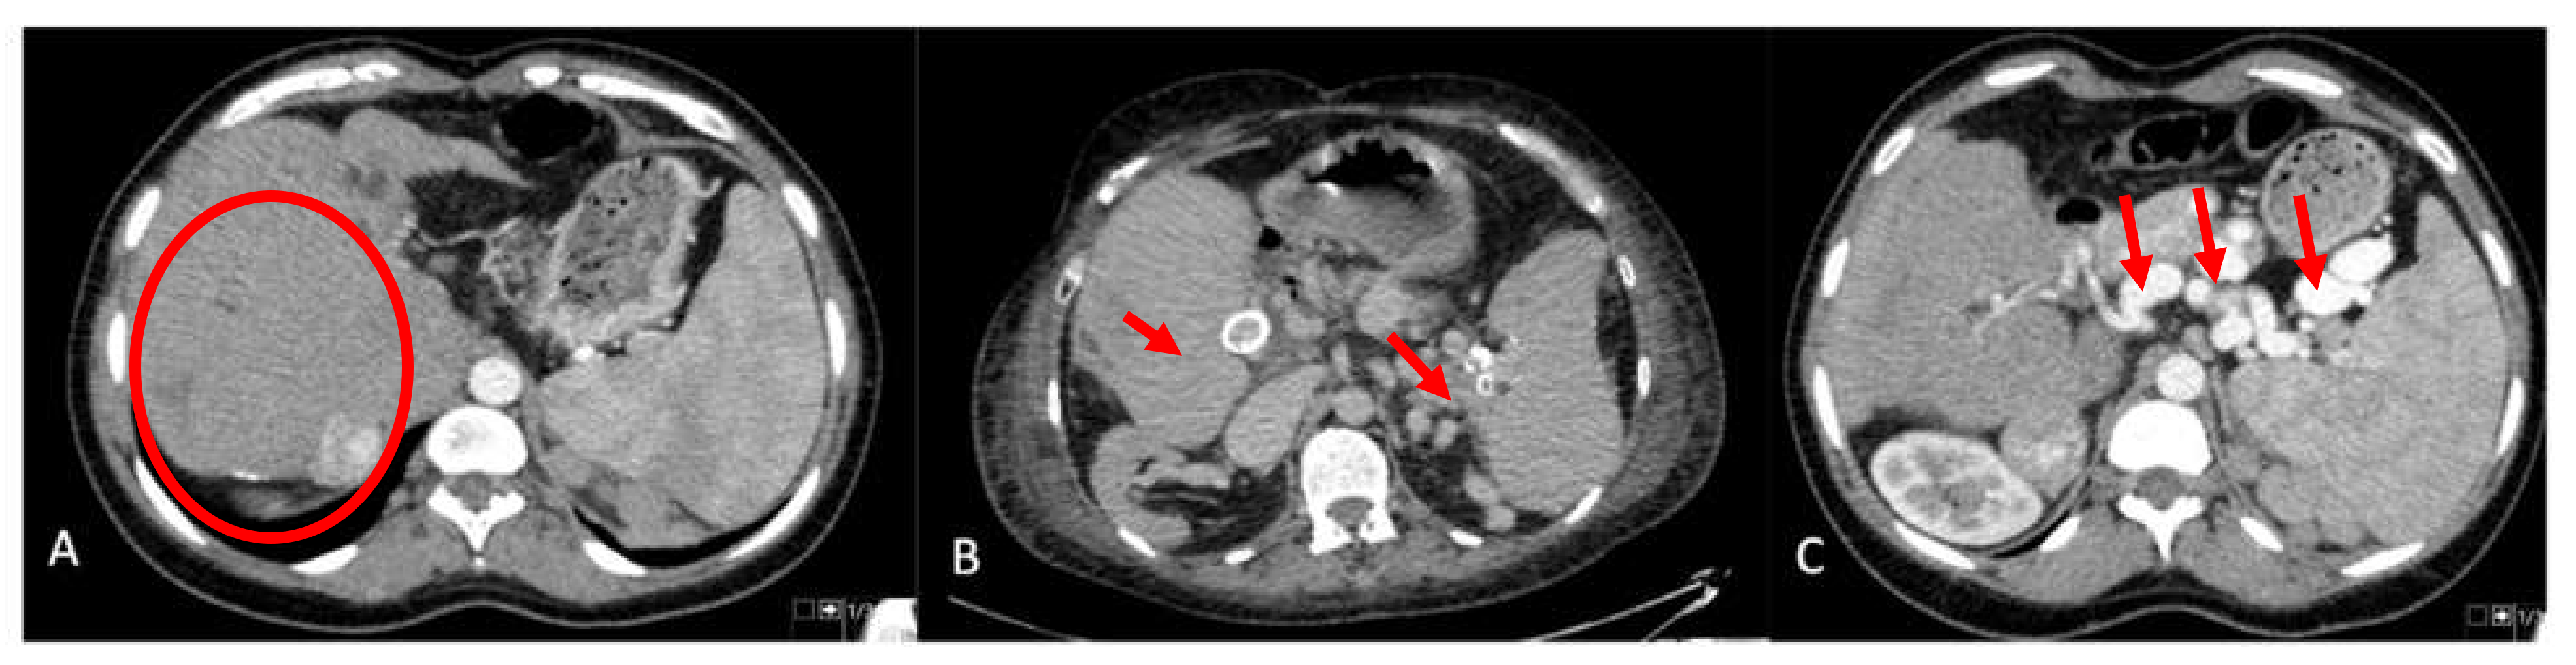

| Arterial aneurysm | |

| Splenic artery | 7 (21.2%) |

| Hepatic artery | 2 (6%) |

| Enlargement of the splenic artery | 18 (52.9%) |

| Intrabdominal variceal shunting | |

| Total number of patients | 24 (68.6%) |

| Retroperitoneal | 22 (64.7%) |

| Perisplenic | 14 (41.2%) |

| Lieno-renal | 9 (26.5%) |

| Left gastric territory | 7 (20.6%) |

| Portal vein findings on US | |

| Low velocity antegrade | 2 (6.1%) |

| Retrograde | 5 (15.2%) |

| No flow | 5 (15.2%) |